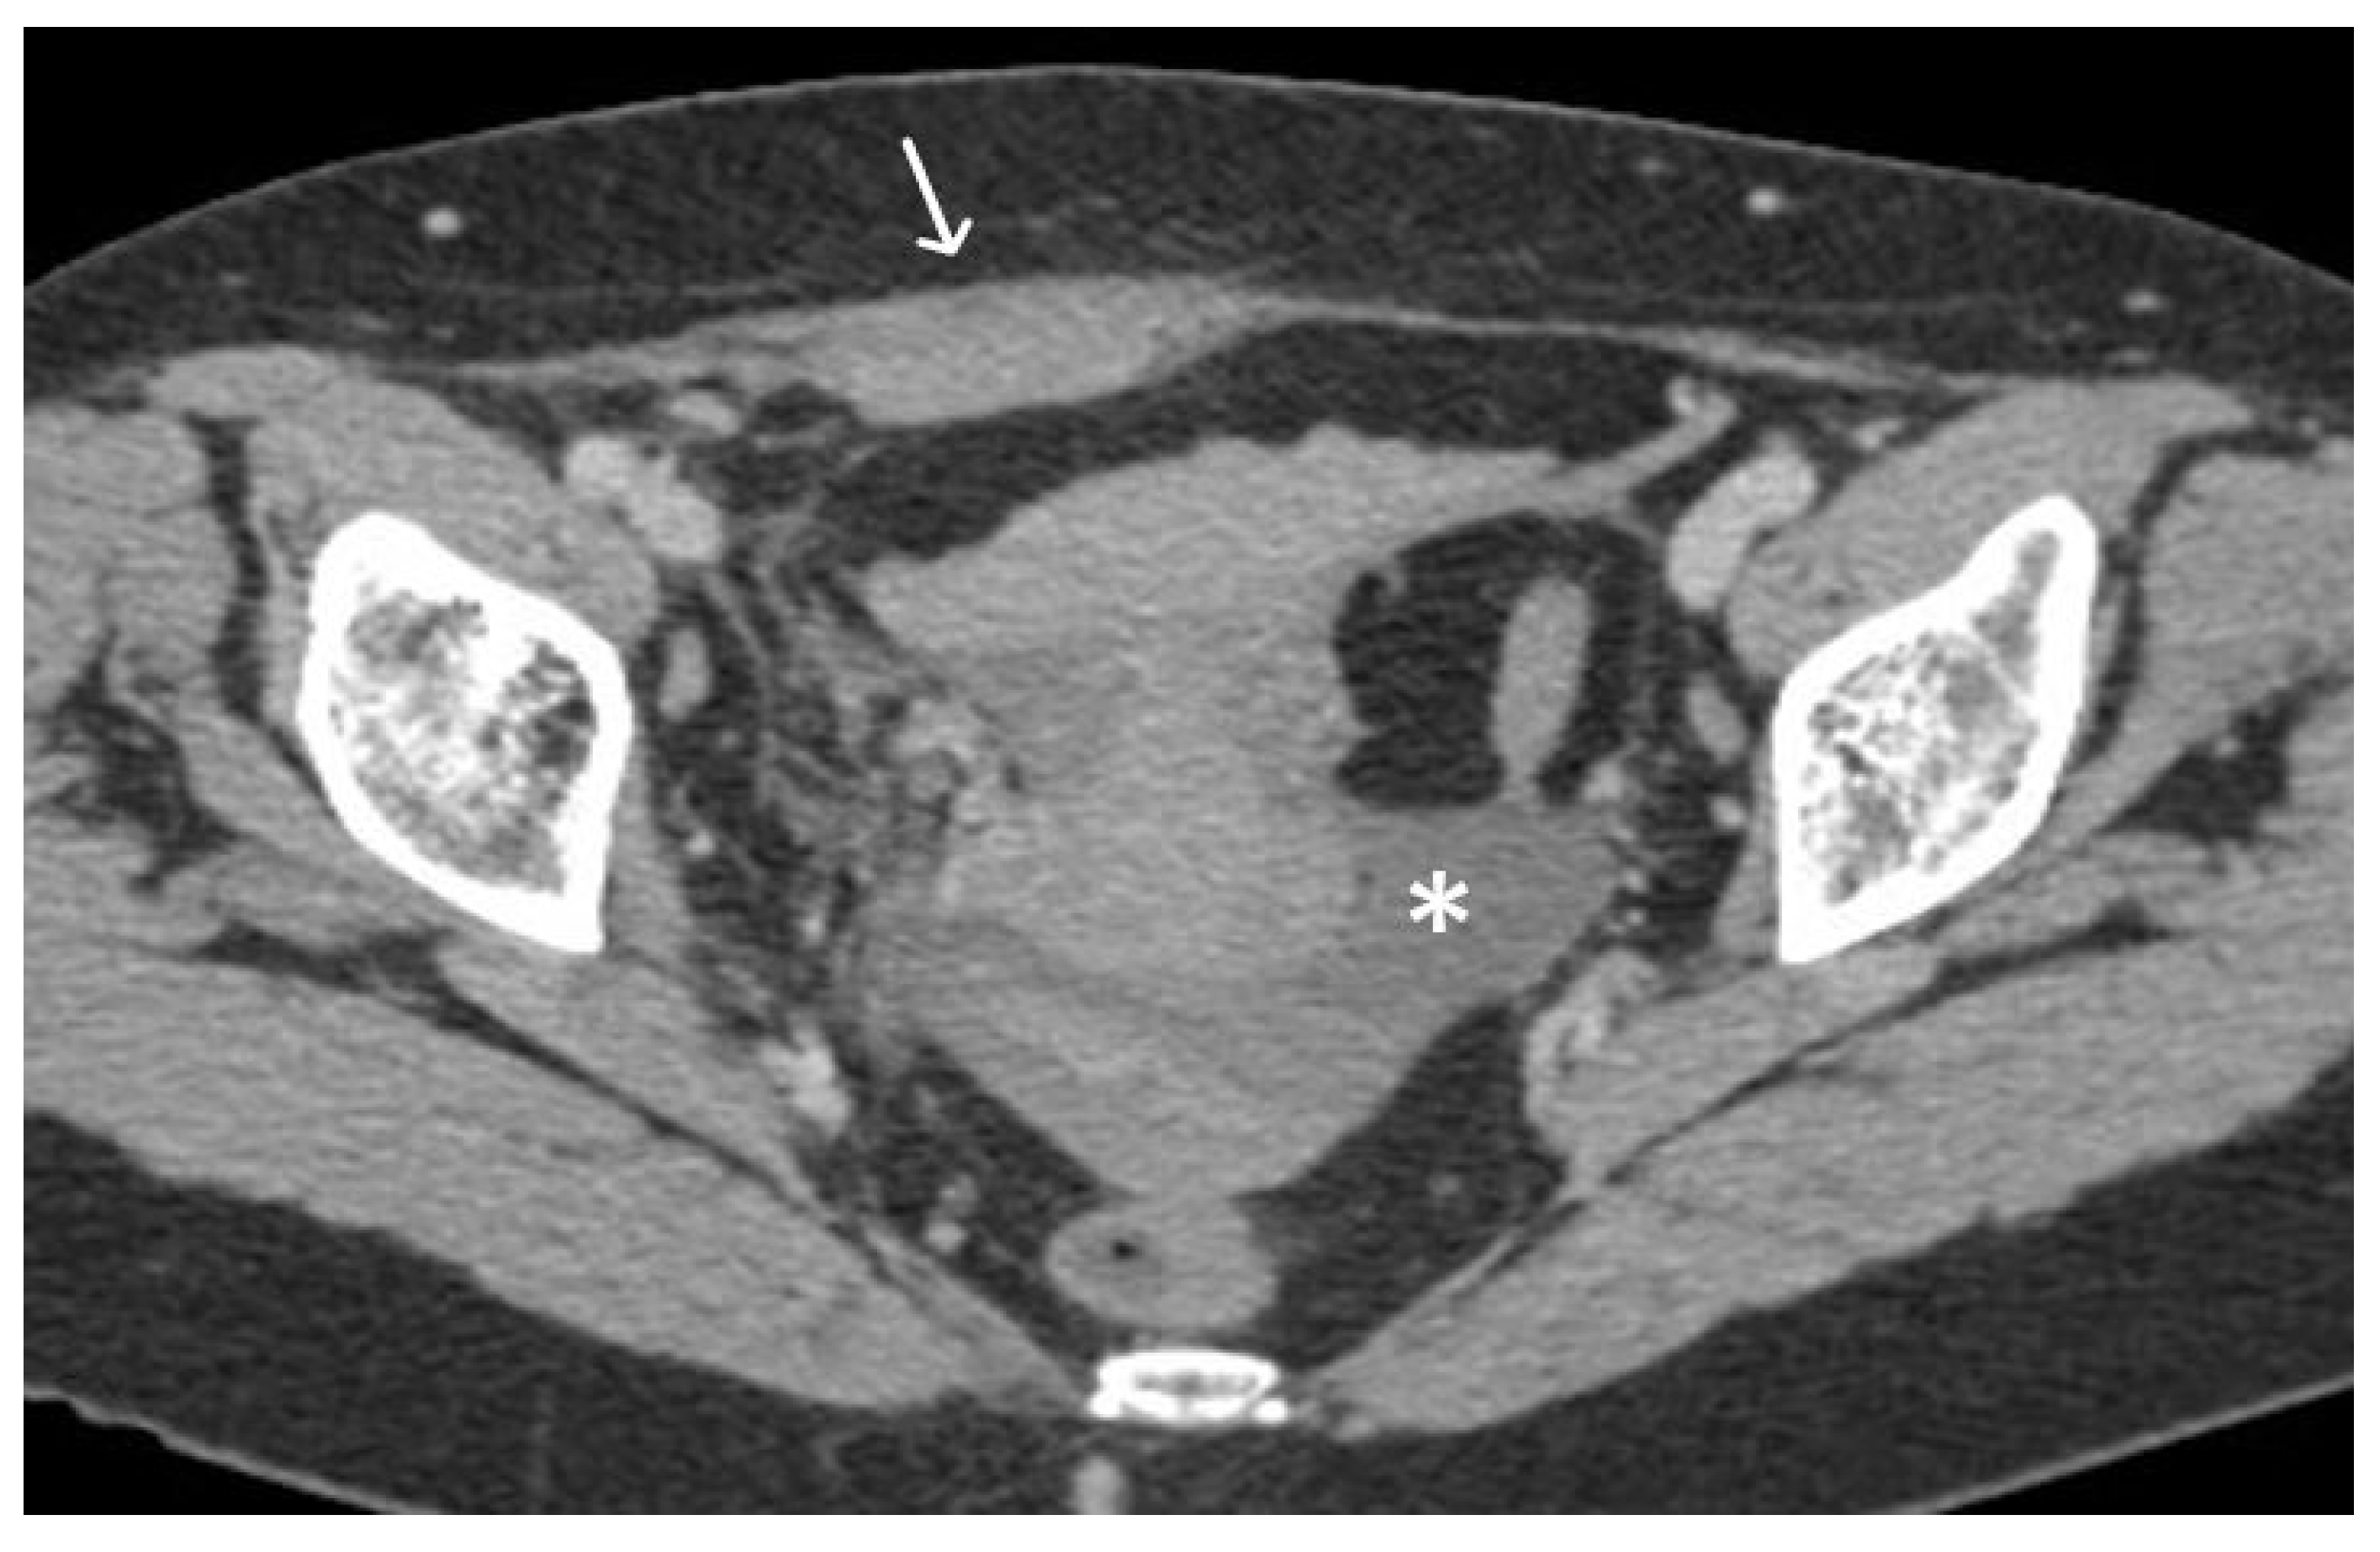

4. Urethral Mesh in Oncological Patients

5. Urethral Mesh Complications

5.2. Long-Term Complications